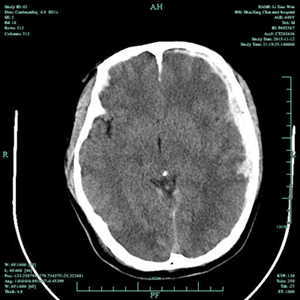

2015年11月12日,49岁的李先生在工地干活时不慎从高处坠落,致头部受伤,当时情况危急,由120送至我院,查头颅CT提示颅内广泛硬膜下出血、脑挫伤、脑疝形成,属于重度颅脑损伤,生命危急。我院神经外科王风永主任当机立断,在全麻下给患者施行左侧额颞顶硬膜下血肿清除+去颅骨瓣减压术,手术顺利。术后在ICU及十二病区全体医护人员的精心治疗和护理下,患者逐渐康复,语言表达、肢体活动、生活自理方面均恢复良好,术后一月顺利出院,并建议患者在家修养一段时间后,尽早返院再行颅骨缺损修补手术。

受伤术前